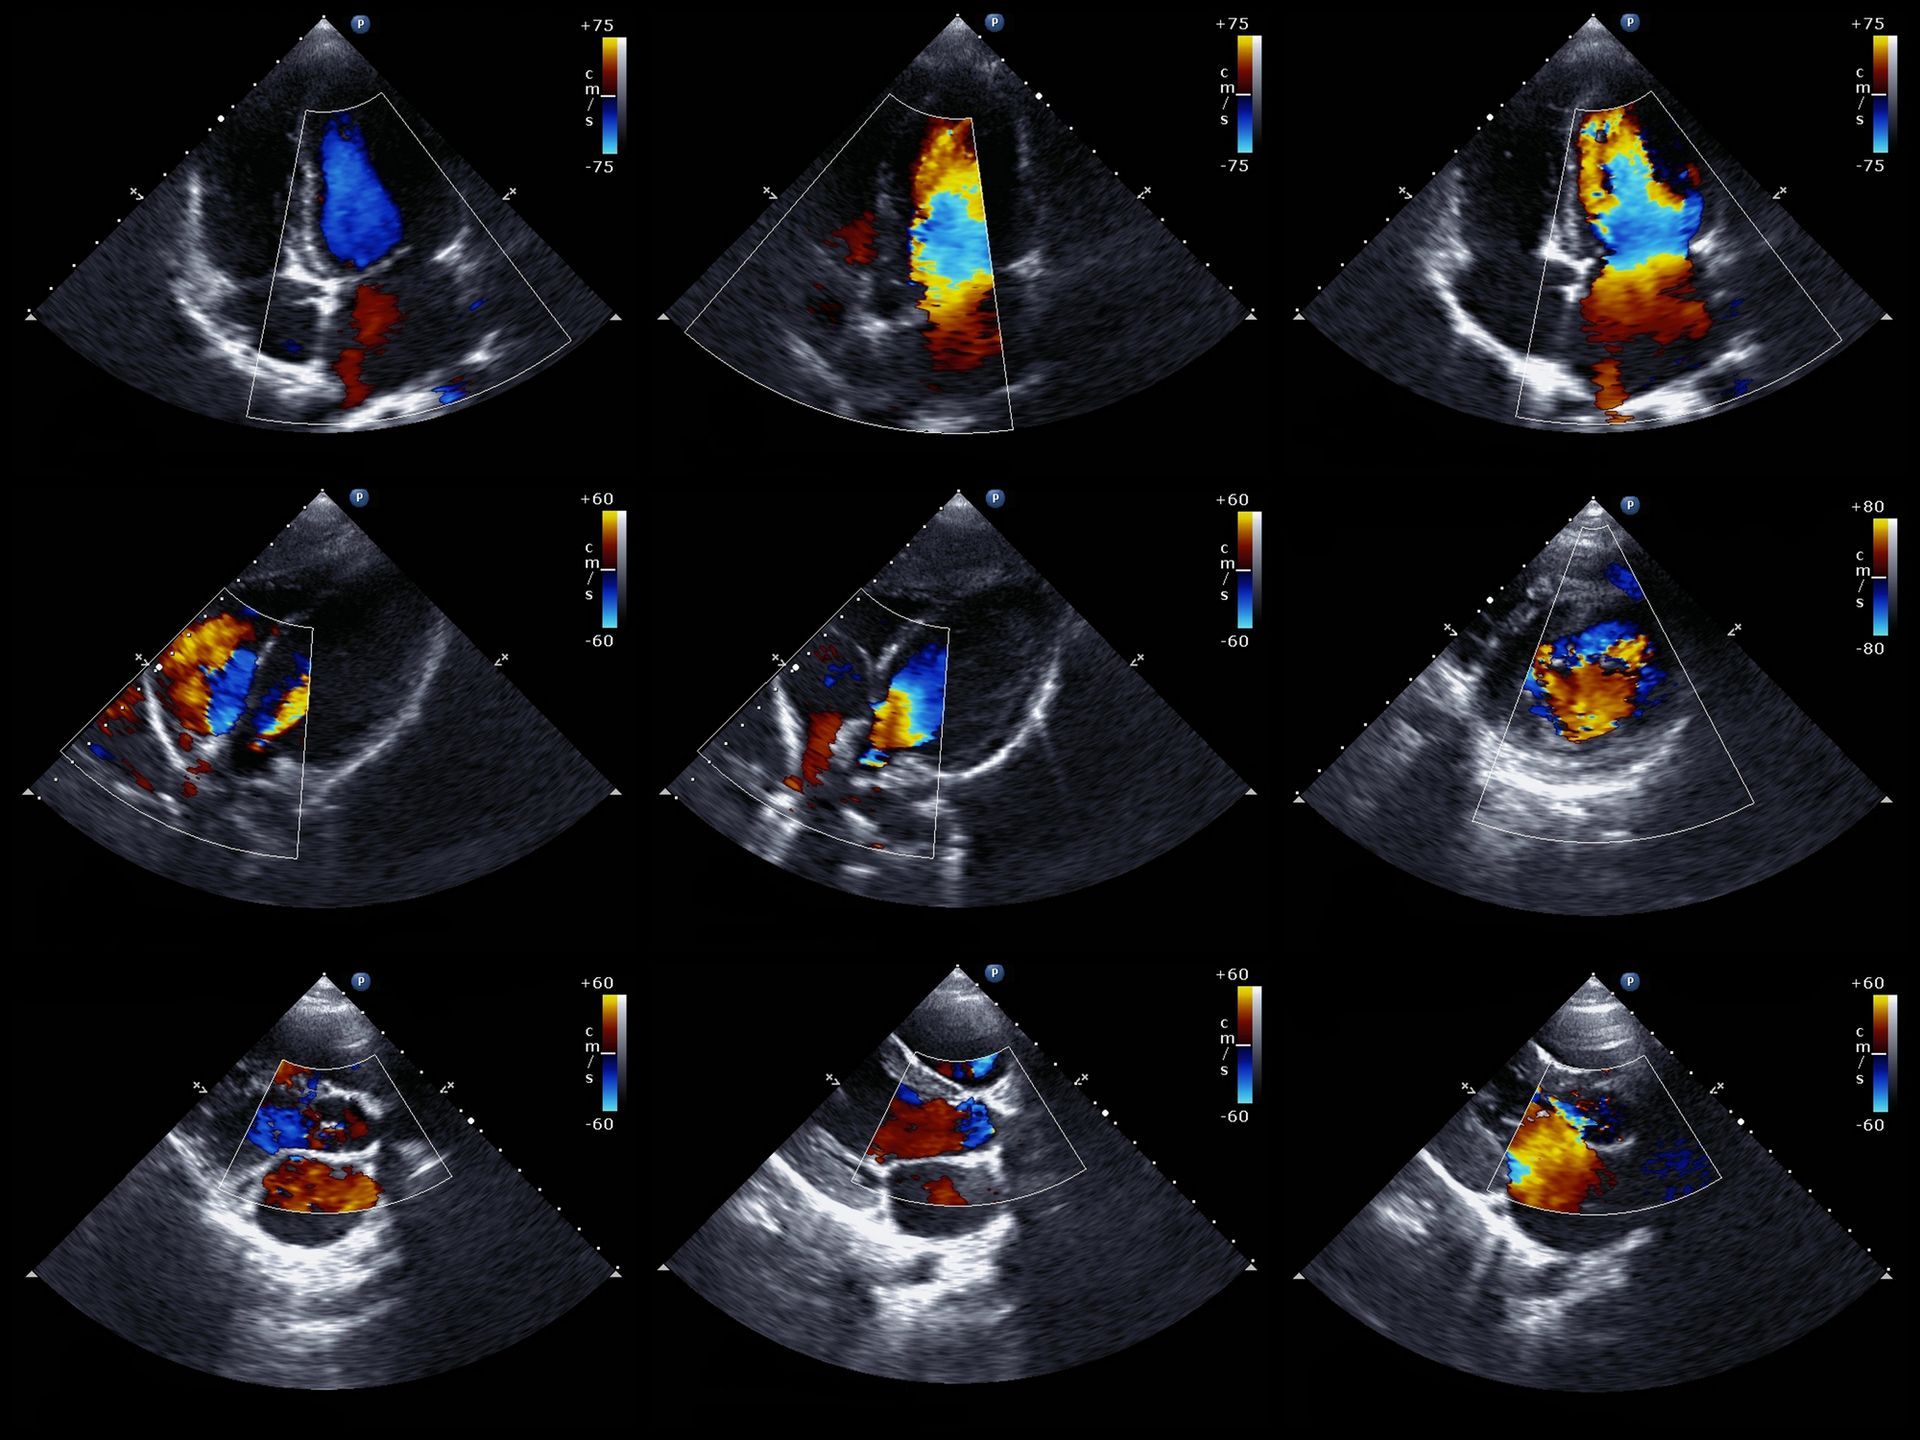

Ecocolordoppler

Questa tecnica avanzata combina l'ecografia con il doppler a colori, consentendo di valutare il flusso sanguigno e la struttura dei vasi.